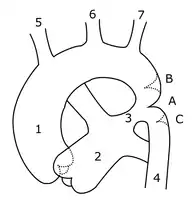

- Preductal coarctation: The narrowing is proximal to the ductus arteriosus. Blood flow to the aorta that is distal to the narrowing is dependent on the ductus arteriosus; therefore severe coarctation can be life-threatening. Preductal coarctation results when an intracardiac anomaly during fetal life decreases blood flow through the left side of the heart, leading to hypoplastic development of the aorta. This is the type seen in approximately 5% of infants with Turner syndrome.[12][13]

- Ductal coarctation: The narrowing occurs at the insertion of the ductus arteriosus. This kind usually appears when the ductus arteriosus closes.

- Postductal coarctation: The narrowing is distal to the insertion of the ductus arteriosus. Even with an open ductus arteriosus, blood flow to the lower body can be impaired. This type is most common in adults. It is associated with notching of the ribs (because of collateral circulation), hypertension in the upper extremities, and weak pulses in the lower extremities. Postductal coarctation is most likely the result of the extension of a muscular artery (ductus arteriosus) into an elastic artery (aorta) during fetal life, where the contraction and fibrosis of the ductus arteriosus upon birth subsequently narrows the aortic lumen.[14]

Sketch showing heart with coarctation of the aorta. A: Coarctation (narrowing) of the aorta. 1:Inferior vena cava, 2:Right pulmonary veins, 3: Right pulmonary artery, 4:Superior vena cava, 5:Left pulmonary artery, 6:Left pulmonary veins, 7:Right ventricle, 8:Left ventricle, 9:Pulmonary artery, 10:Aorta Schematic drawing of alternative locations of a coarctation of the aorta, relative to the ductus arteriosus. A: Ductal coarctation, B: Preductal coarctation, C: Postductal coarctation. 1: Aorta ascendens, 2: Arteria pulmonalis, 3: Ductus arteriosus, 4: Aorta descendens, 5: Truncus brachiocephalicus, 6: Arteria carotis communis sinistra, 7: Arteria subclavia sinistra

Schematic drawing of alternative locations of a coarctation of the aorta, relative to the ductus arteriosus. A: Ductal coarctation, B: Preductal coarctation, C: Postductal coarctation. 1: Aorta ascendens, 2: Arteria pulmonalis, 3: Ductus arteriosus, 4: Aorta descendens, 5: Truncus brachiocephalicus, 6: Arteria carotis communis sinistra, 7: Arteria subclavia sinistra 3D model of coarctation of aorta